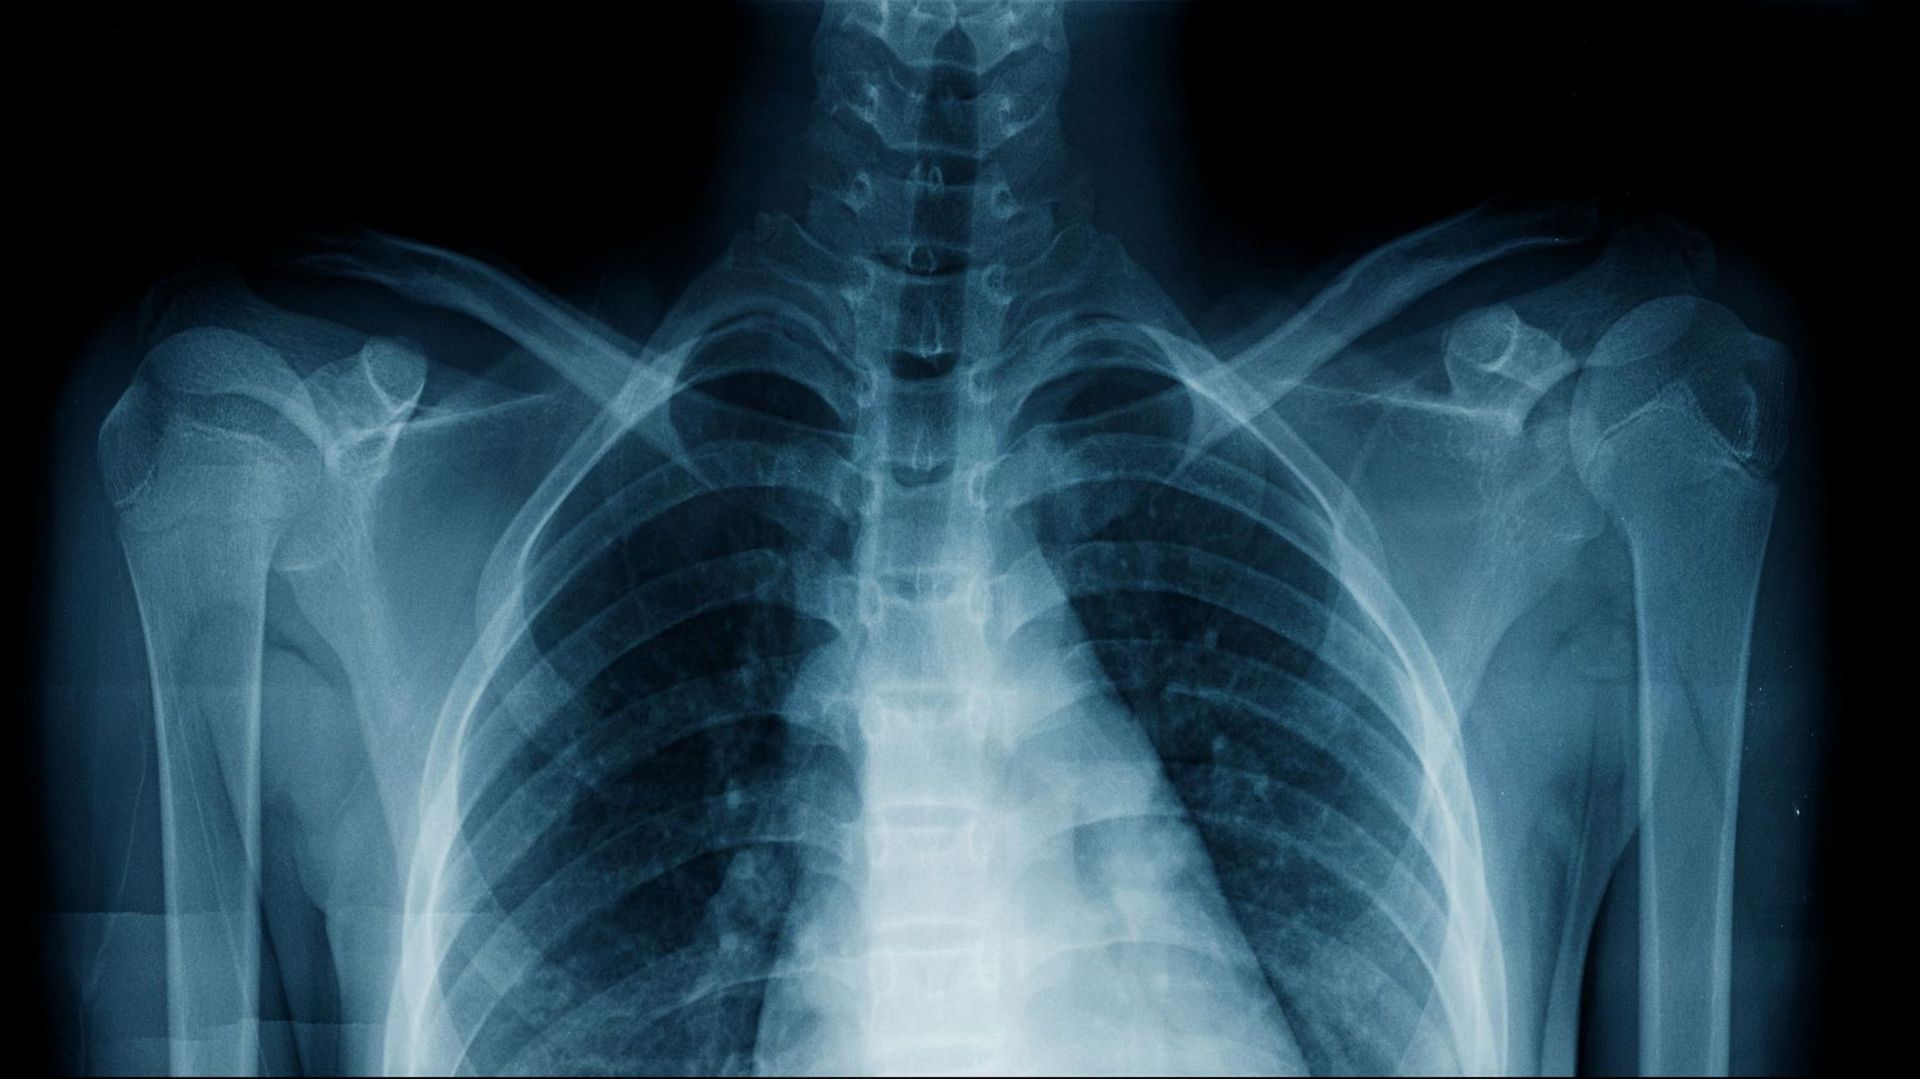

Une IA reconnait l’origine ethnique d’un humain sur les rayons X et on ne comprend pas comment - RTBF Actus Des scientifiques de l’Université de Harvard ont découvert que les programmes d’IA peuvent déterminer la couleur de... RTBF